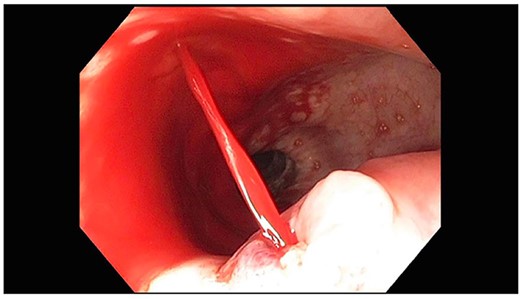

A 71-year-old male with past medical history of type 2 diabetes and hypertension presented to the emergency department at St. Joseph’s University Medical Center with severe respiratory distress. On nonrebreather, the patient’s oxygen saturation was 49%. The patient was subsequently intubated. Evaluation revealed pneumonia secondary to COVID-19 leading patient to be intubated on ventilator support for 4 weeks. During this time patient was maintained on enteral feeding through nasogastric tube, and was on gastrointestinal prophylaxis Protonix 40 mg daily for the duration of his admission. Ultimately, the patient made full recovery and was sent home; however, approximately 3 weeks later, he presented to the emergency department due to syncope. The patient experienced large-volume bright red hematemesis. He became hypotensive and was transfused three units of packed red blood cells and started on pressors. The patient was intubated and transferred to the intensive care unit (ICU) with acute blood loss anemia and hypovolemic shock. Here, an esophagogastroduodenoscopy (EGD) was performed revealing midesophageal bleed (Fig. 1). Hemostasis was achieved with clipping; however, post-procedurally, the patient again became hypotensive. Repeat EGD showed a nonbleeding esophageal ulcer with three clips in good position (Fig. 2). Computed tomography (CT) angiogram of the thorax was performed revealing an actively bleeding aberrant right subclavian artery perforating into the esophagus (Figs 3 and 4). The right subclavian artery was noted to be of normal caliber without ectasia or aneurism and the esophagus was free of any other pathology. Thoracic and vascular surgery were consulted; however, the bleed was deemed of nonsurvivable pathology due to comorbidities and current clinical status. Ultimately, the family of the patient decided to withdraw care and the patient passed.